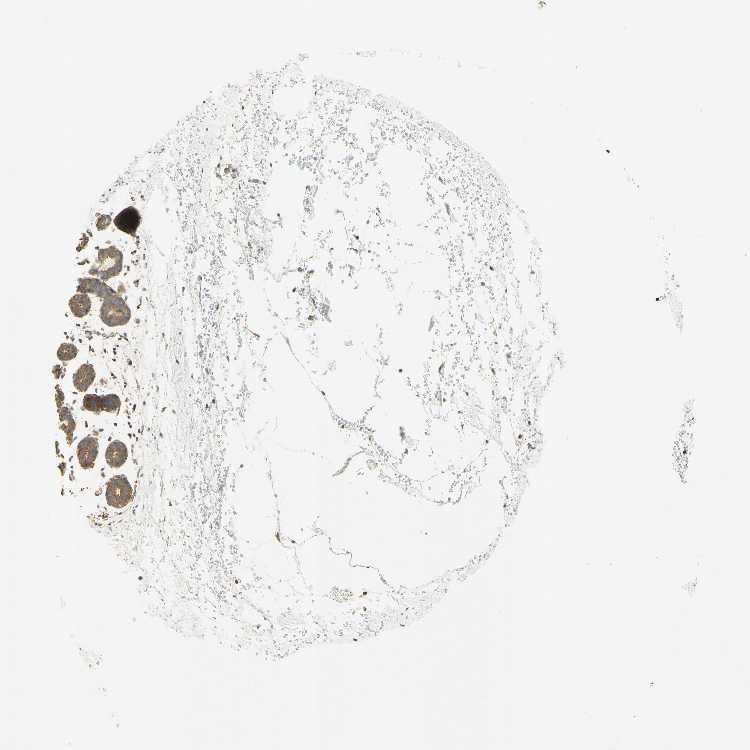

BREAST - Antibody stainingi

Antibody staining in the annotated cell types in the current human tissue is reported as not detected, low, medium, or high, based on conventional immunohistochemistry profiling in selected tissues. This score is based on the combination of the staining intensity and fraction of stained cells.

Each image is clickable and will lead to virtual microscopy that enables deeper exploration of all samples and also displays staining intensity scores, fraction scores and subcellular localization as well as patient and tissue information for each sample.

Antibody HPA000426Antibody CAB010373

Adipocytes Not detectedNot detected

Glandular cells MediumMedium

Myoepithelial cells MediumMedium